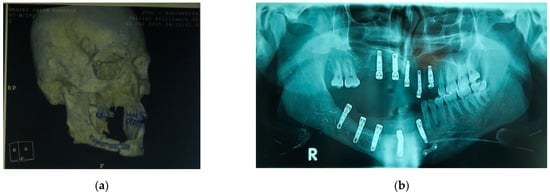

Figure 8.

(a) 3D imaging before prosthetic treatment; (b) Rx imaging after implant surgery. Three-dimensional, (3D).

In the last case, a high-velocity ballistic trauma caused the loss of alveolar bone in different areas of the jaw with loss of teeth in the first, second, and fourth quadrant and of adjacent soft tissue. The patient presented an extensive soft tissue depression of the cheek with a retracting and hypertrophic scar in the trauma zone. During the surgery, the traumatized alveolar bone zone was cleaned; then, an alveolar resection of quad. I and quad. IV was performed followed by the second reconstructive surgery of the area, carried out with osteomyocutaneous free iliac crest flap. Four months after first surgery, ten implants, namely “Zimmer Trabecular Metal”, were inserted in sites to be rehabilitated. After four months, healing screws were inserted, and six months later, the patient finalized the implant-supported prosthetic rehabilitation. In both the second and third case, the final prosthesis consisted of a titanium primary structure and a composite-coated secondary structure that reproduced teeth with or without gingiva (Figure 7, Figure 8 and Figure 9).